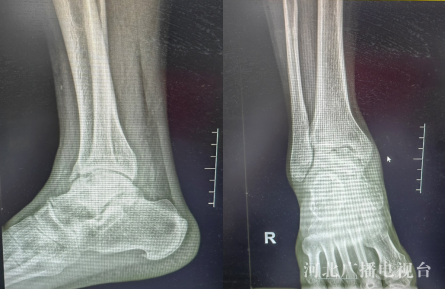

X线检查可见患者出现右踝关节退变,距骨坏死